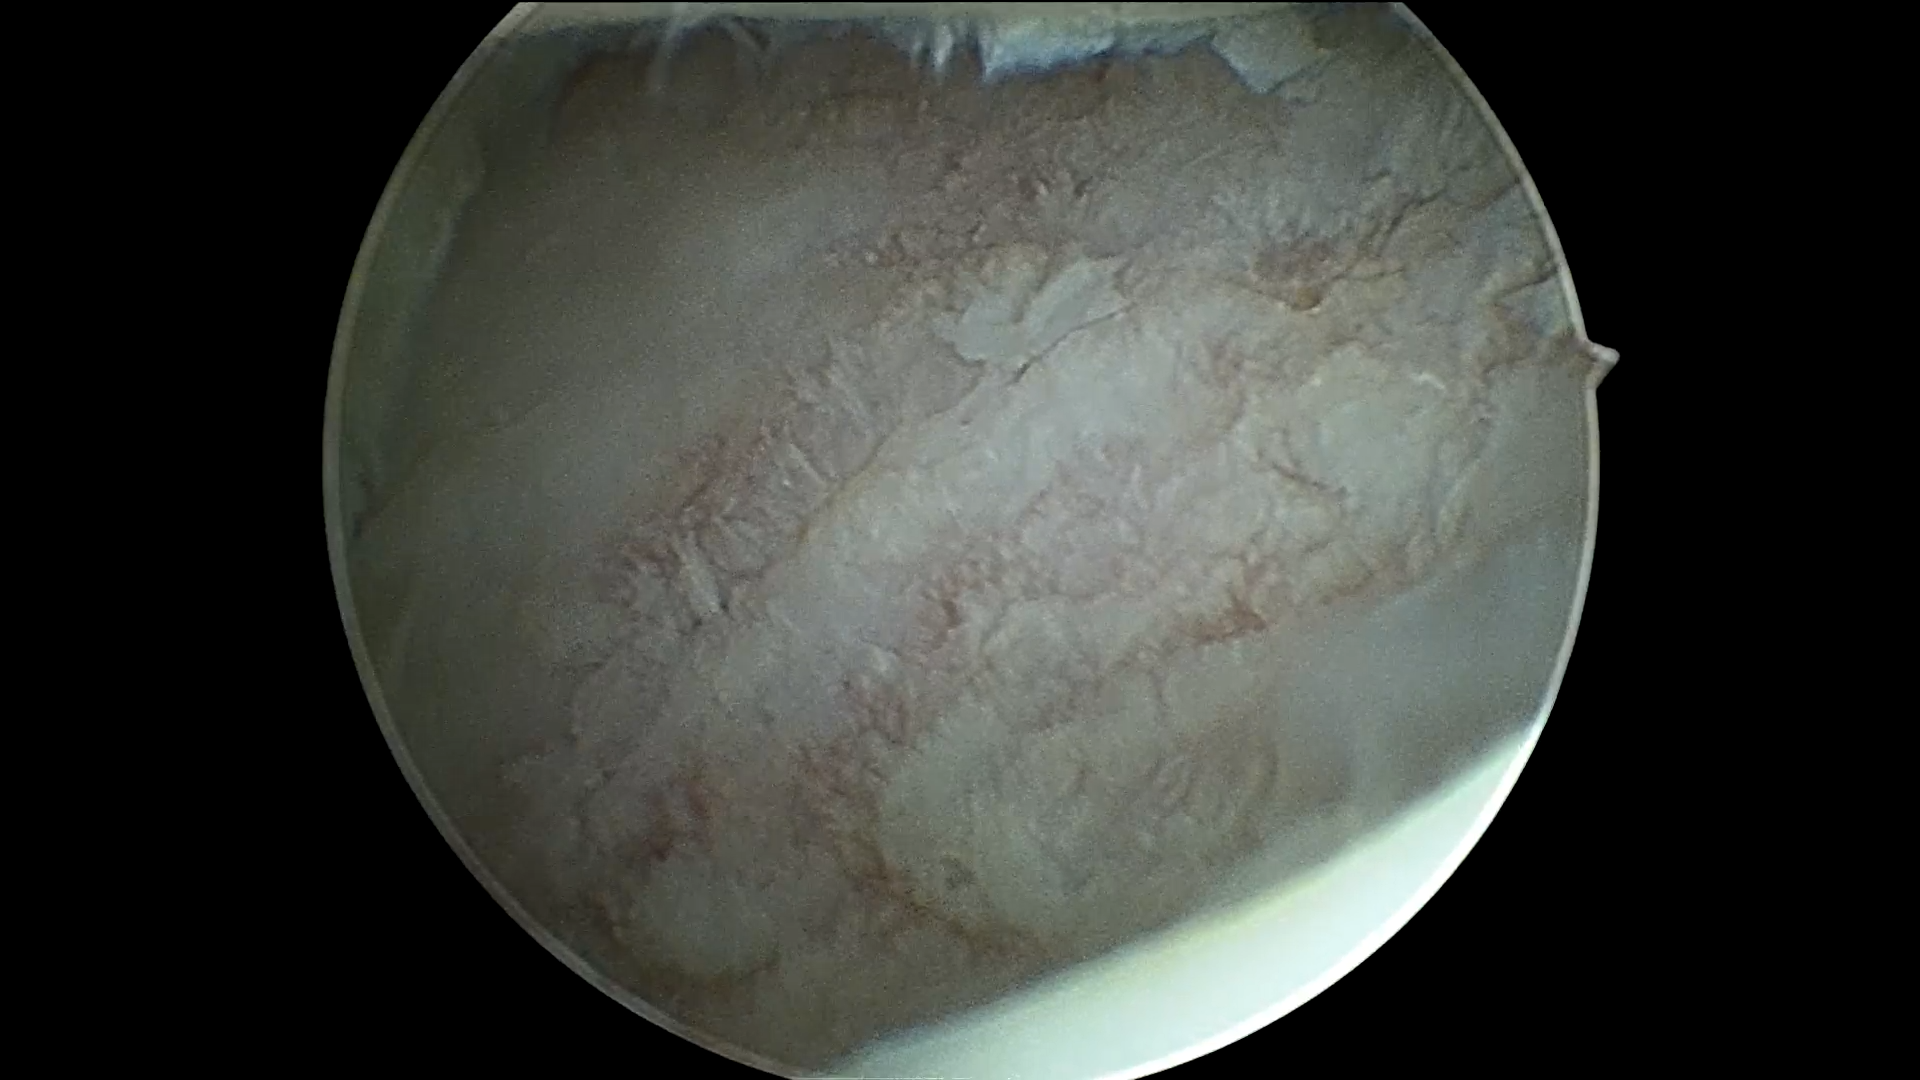

关节镜下见滑车软骨大面积损伤,软骨下骨暴露

关节镜下微骨折术---可见软骨下骨“油滴”溢出

松开止血带后,可见微骨折孔,血性溢出,后期形成血凝块,持续被动活动产生应力,诱导其形成纤维软骨,覆盖缺损区域,完成软骨损伤修复!